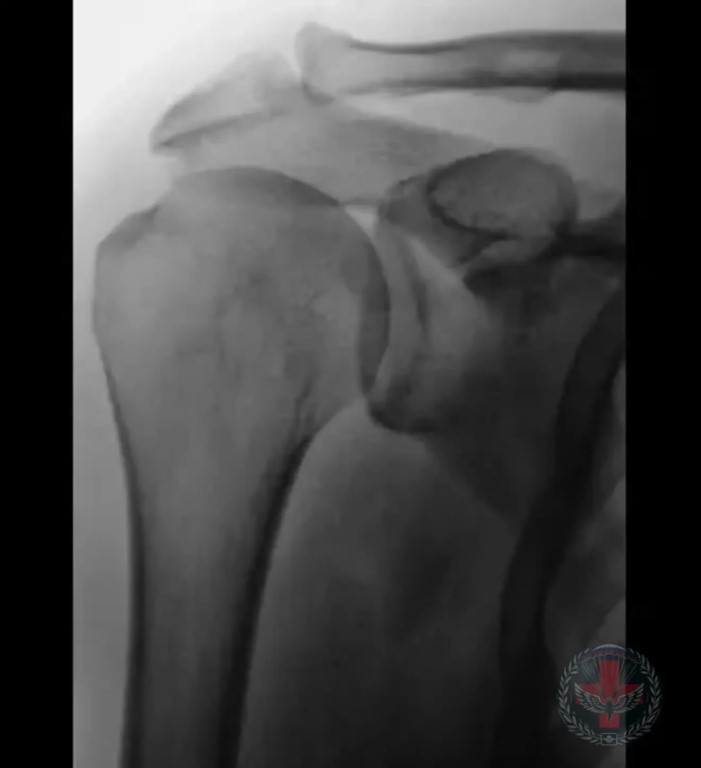

Фото 🪂 Артроз: невидимый враг суставов и его рентгенологические проявления Артроз, или остеоартроз – это дегенеративное заболевание суставов, которое поражает хрящевую ткань, приводя к ее разрушению. Важность своевременной диагностики артроза невозможно переоценить, ведь именно рентгенологическое исследование позволяет выявить патологические изменения на ранних стадиях, когда лечение наиболее эффективно. Рентгенологически выделяют несколько стадий заболевания: Стадия 1 (начальная): Минимальные изменения, которые могут быть незаметны невооруженным глазом. На рентгенограммах могут наблюдаться незначительное сужение суставной щели и появление мелких остеофитов (костных наростов) по краям суставных поверхностей. Стадия 2 (умеренная): Суставная щель становится более узкой, остеофиты увеличиваются в размерах. Могут появиться субхондральные кисты (полости, заполненные жидкостью, под хрящом) и деформации суставных поверхностей. Стадия 3 (выраженная): Значительное сужение или полное отсутствие суставной щели, крупные и деформирующие остеофиты. Субхондральные кисты становятся более многочисленными и крупными. Наблюдаются выраженные изменения формы сустава. Стадия 4 (терминальная): Практически полное разрушение хряща, полное отсутствие суставной щели, выраженная деформация суставных поверхностей. Анкилоз (сращение) сустава может быть следствием последней стадии. Рентгенография является «золотым стандартом» в диагностике артроза. Она позволяет: 🔷Оценить степень сужения суставной щели – ключевой показатель износа хряща. Выявить наличие и размер остеофитов, которые могут вызывать боль и ограничение движений. 🔷Обнаружить субхондральные кисты, свидетельствующие о глубоких изменениях в костной ткани. 🔷Оценить деформацию сустава и степень повреждения костных структур. 🕒Своевременное рентгенологическое обследование позволяет поставить точный диагноз, определить стадию артроза и назначить адекватное лечение, направленное на замедление прогрессирования заболевания и улучшение качества жизни пациента 📞 По вопросам и подаче заявок — @omedoa39 Поддержать наш канал можно голосами по этой ссылке: 👉🏻 t.me/boost/airborne_medical AIRBORNE_MEDICAL ПОДПИСАТЬСЯ 🪂